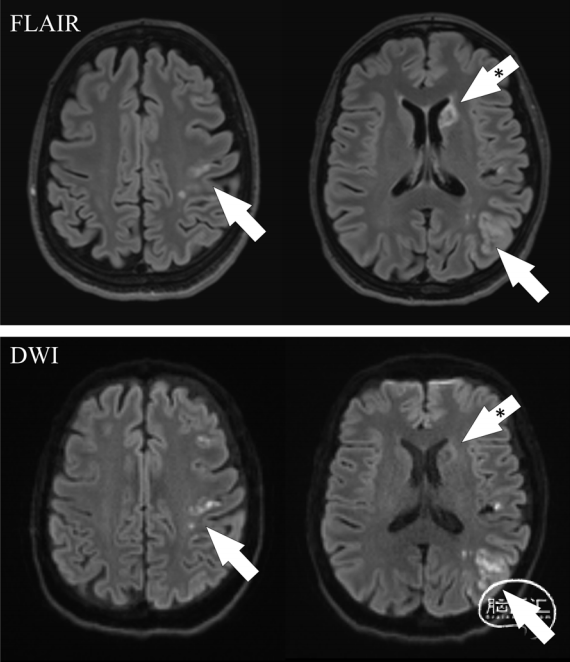

一位54岁的女性因为持续性的右侧感觉-运动型面臂综合征2天来到急诊。除了吸烟外没有其他主要心血管风险因素。她BMI正常,没有高血压、高血脂、糖尿病、神经或心血管事件的病史。此外,她也没有使用含雌激素的口服避孕药,家族史中也没有脑血管事件。入院时的神经学检查显示右下面肌麻痹(NIHSS=2),头部CT扫描和血液检查均正常,怀疑是轻微中风,因此患者开始了双重抗血小板治疗(DAPT),并被收入卒中单元。脑部MRI扫描显示左中大脑动脉血管领域内有多个小的异步皮质-皮下缺血灶,以及左尾状核头部的亚急性/慢性缺血病变(图1);持续心电图和心脏超声检查未发现异常。

图1. FLAIR和DWI序列显示在左大脑中动脉的Heubner返动脉供血区(白色箭头)和尾状核头部的亚急性/慢性病变的多个病变(星号标记的箭头)。所有的缺血性病变都在左内颈动脉动脉供血区内。